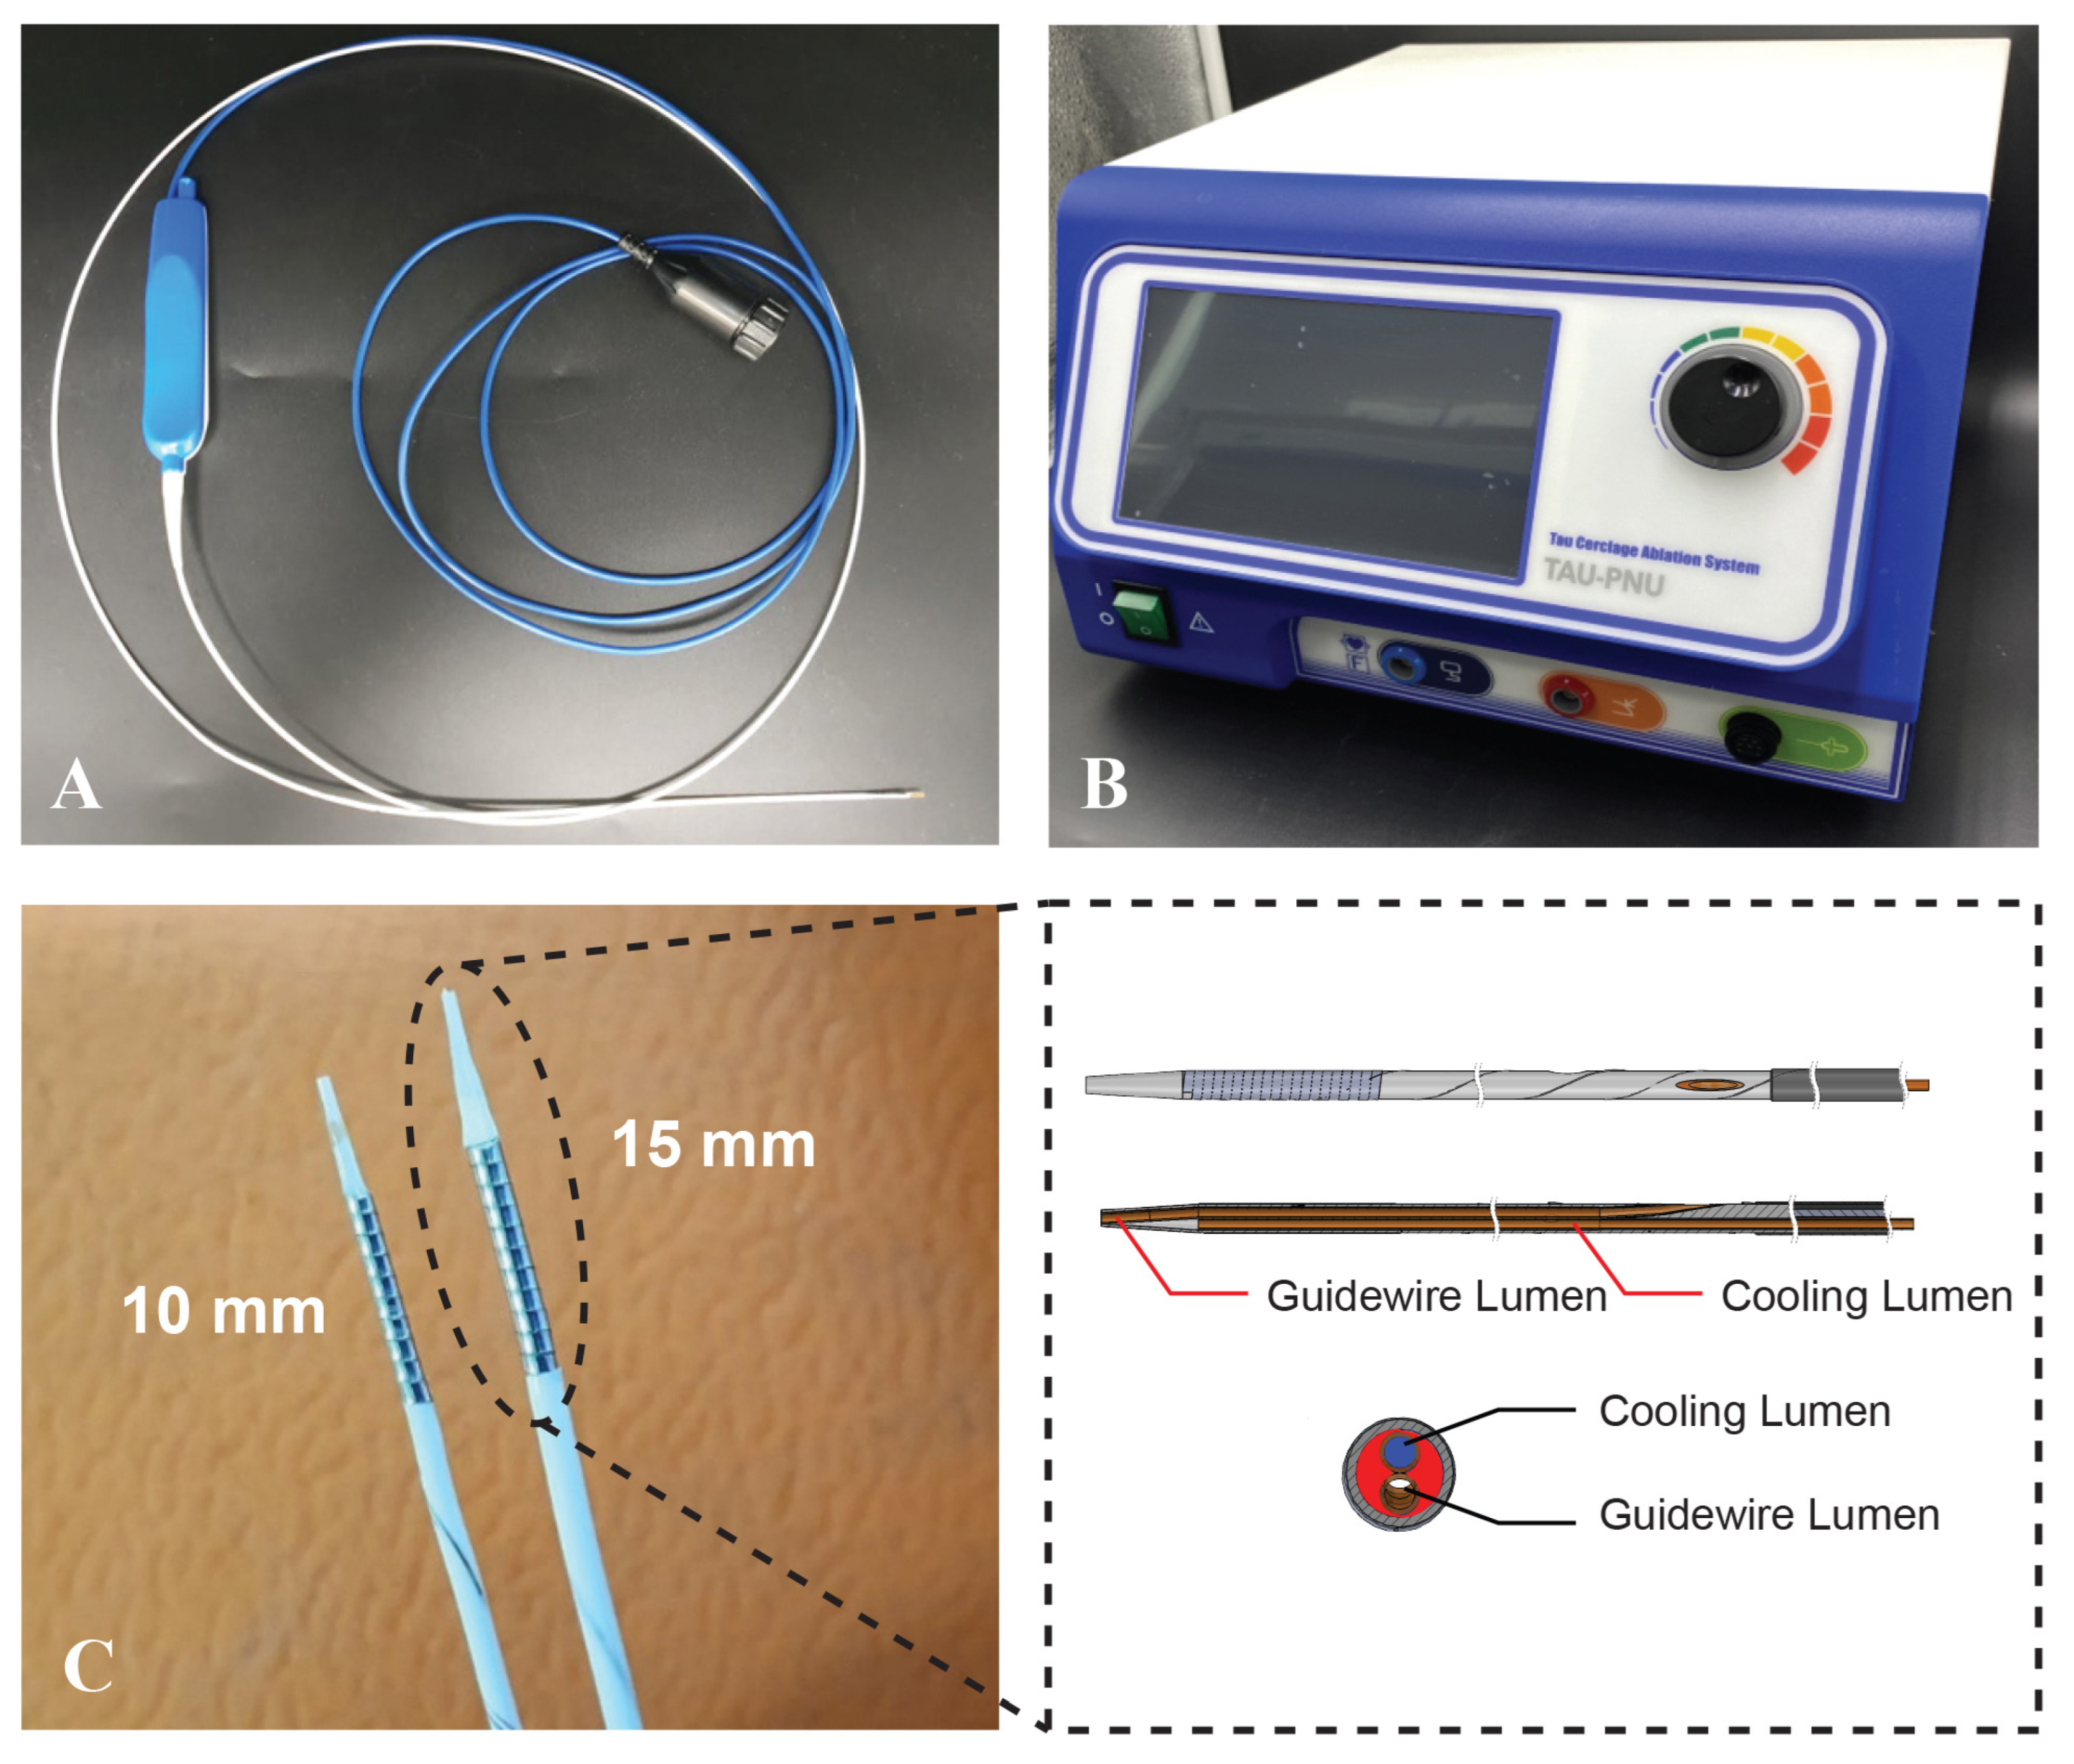

2.1. TIRA-HOCM Device